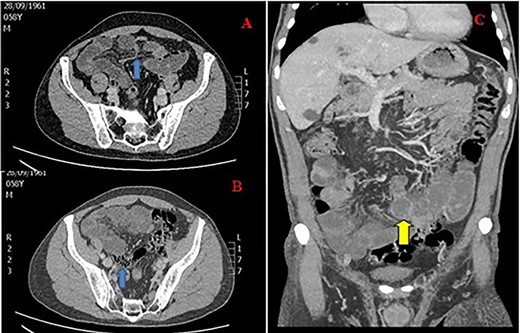

Vital signs were as follows: blood pressure (BP): 163/93 mmHg, heart rate (HR): 80/min, respiratory rate (RR): 14/min, SO2: 99% and temperature (T): 36.5°C. Laboratory studies were unremarkable. A contrast-enhanced CT of the abdomen was performed, and it showed distended jejunal and ileum loops with a transition point in the right iliac fossa after which ileal loops, as well as the large bowel, were collapsed. The small bowel feces sign was also observed. The CT of the abdomen corroborated the diagnosis of SBO and indicated a close loop obstruction (Fig. 1).

CT of the abdomen in a 59-year-old male with SBO; (A) transition point in the right iliac fossa (arrow), (B) feces sign (arrow) and (C) close loop obstruction (arrow).

The patient was then transferred to the operating room for exploratory laparotomy via a midline incision. A congenital band obstructing the ileum was observed. This anomalous band extending from mesentery to ileum caused a small window through which internal herniation of the small bowel and obstruction occurred. No signs of bowel ischemia or peritonitis were noted. The band was ligated and divided. The patient recovered uneventfully, and he was discharged after 3 days.